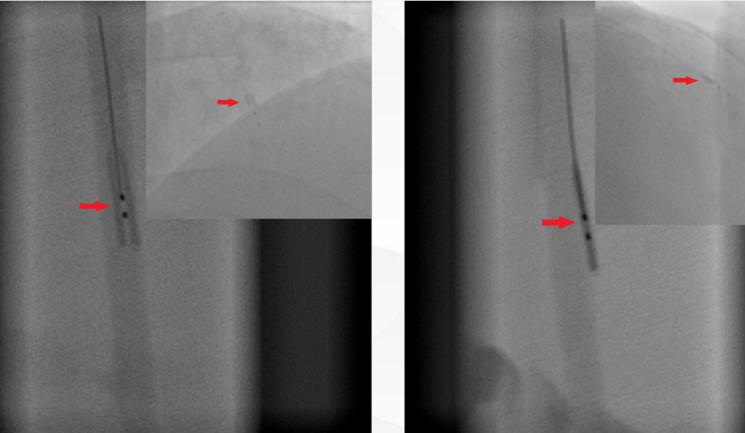

ADR系统包括CrossBoss导管及Stingray球囊,由于CrossBoss导管基本可被Corsair微导管取代,目前应用较少,在此不再赘述。Stingray球囊具有独特的自定向球囊,带有扁平形状球囊体部,设计有2导丝出口,以180度角对称分布在扁平球囊两面,用于真腔瞄准(见图1)。如果导丝进入“血管结构内”,无法进入血管真腔,纯造影剂充分预准备Stingray球囊(在此不再赘述Stingray球囊预准备),送入Stingray球囊,纯造影剂压力泵起4-6atm,找到单轨征,逆向造影指导下确定穿刺方向,硬导丝试错性穿刺进入血管真腔(图2、3)。

图3(左侧双轨征,右侧单轨征)